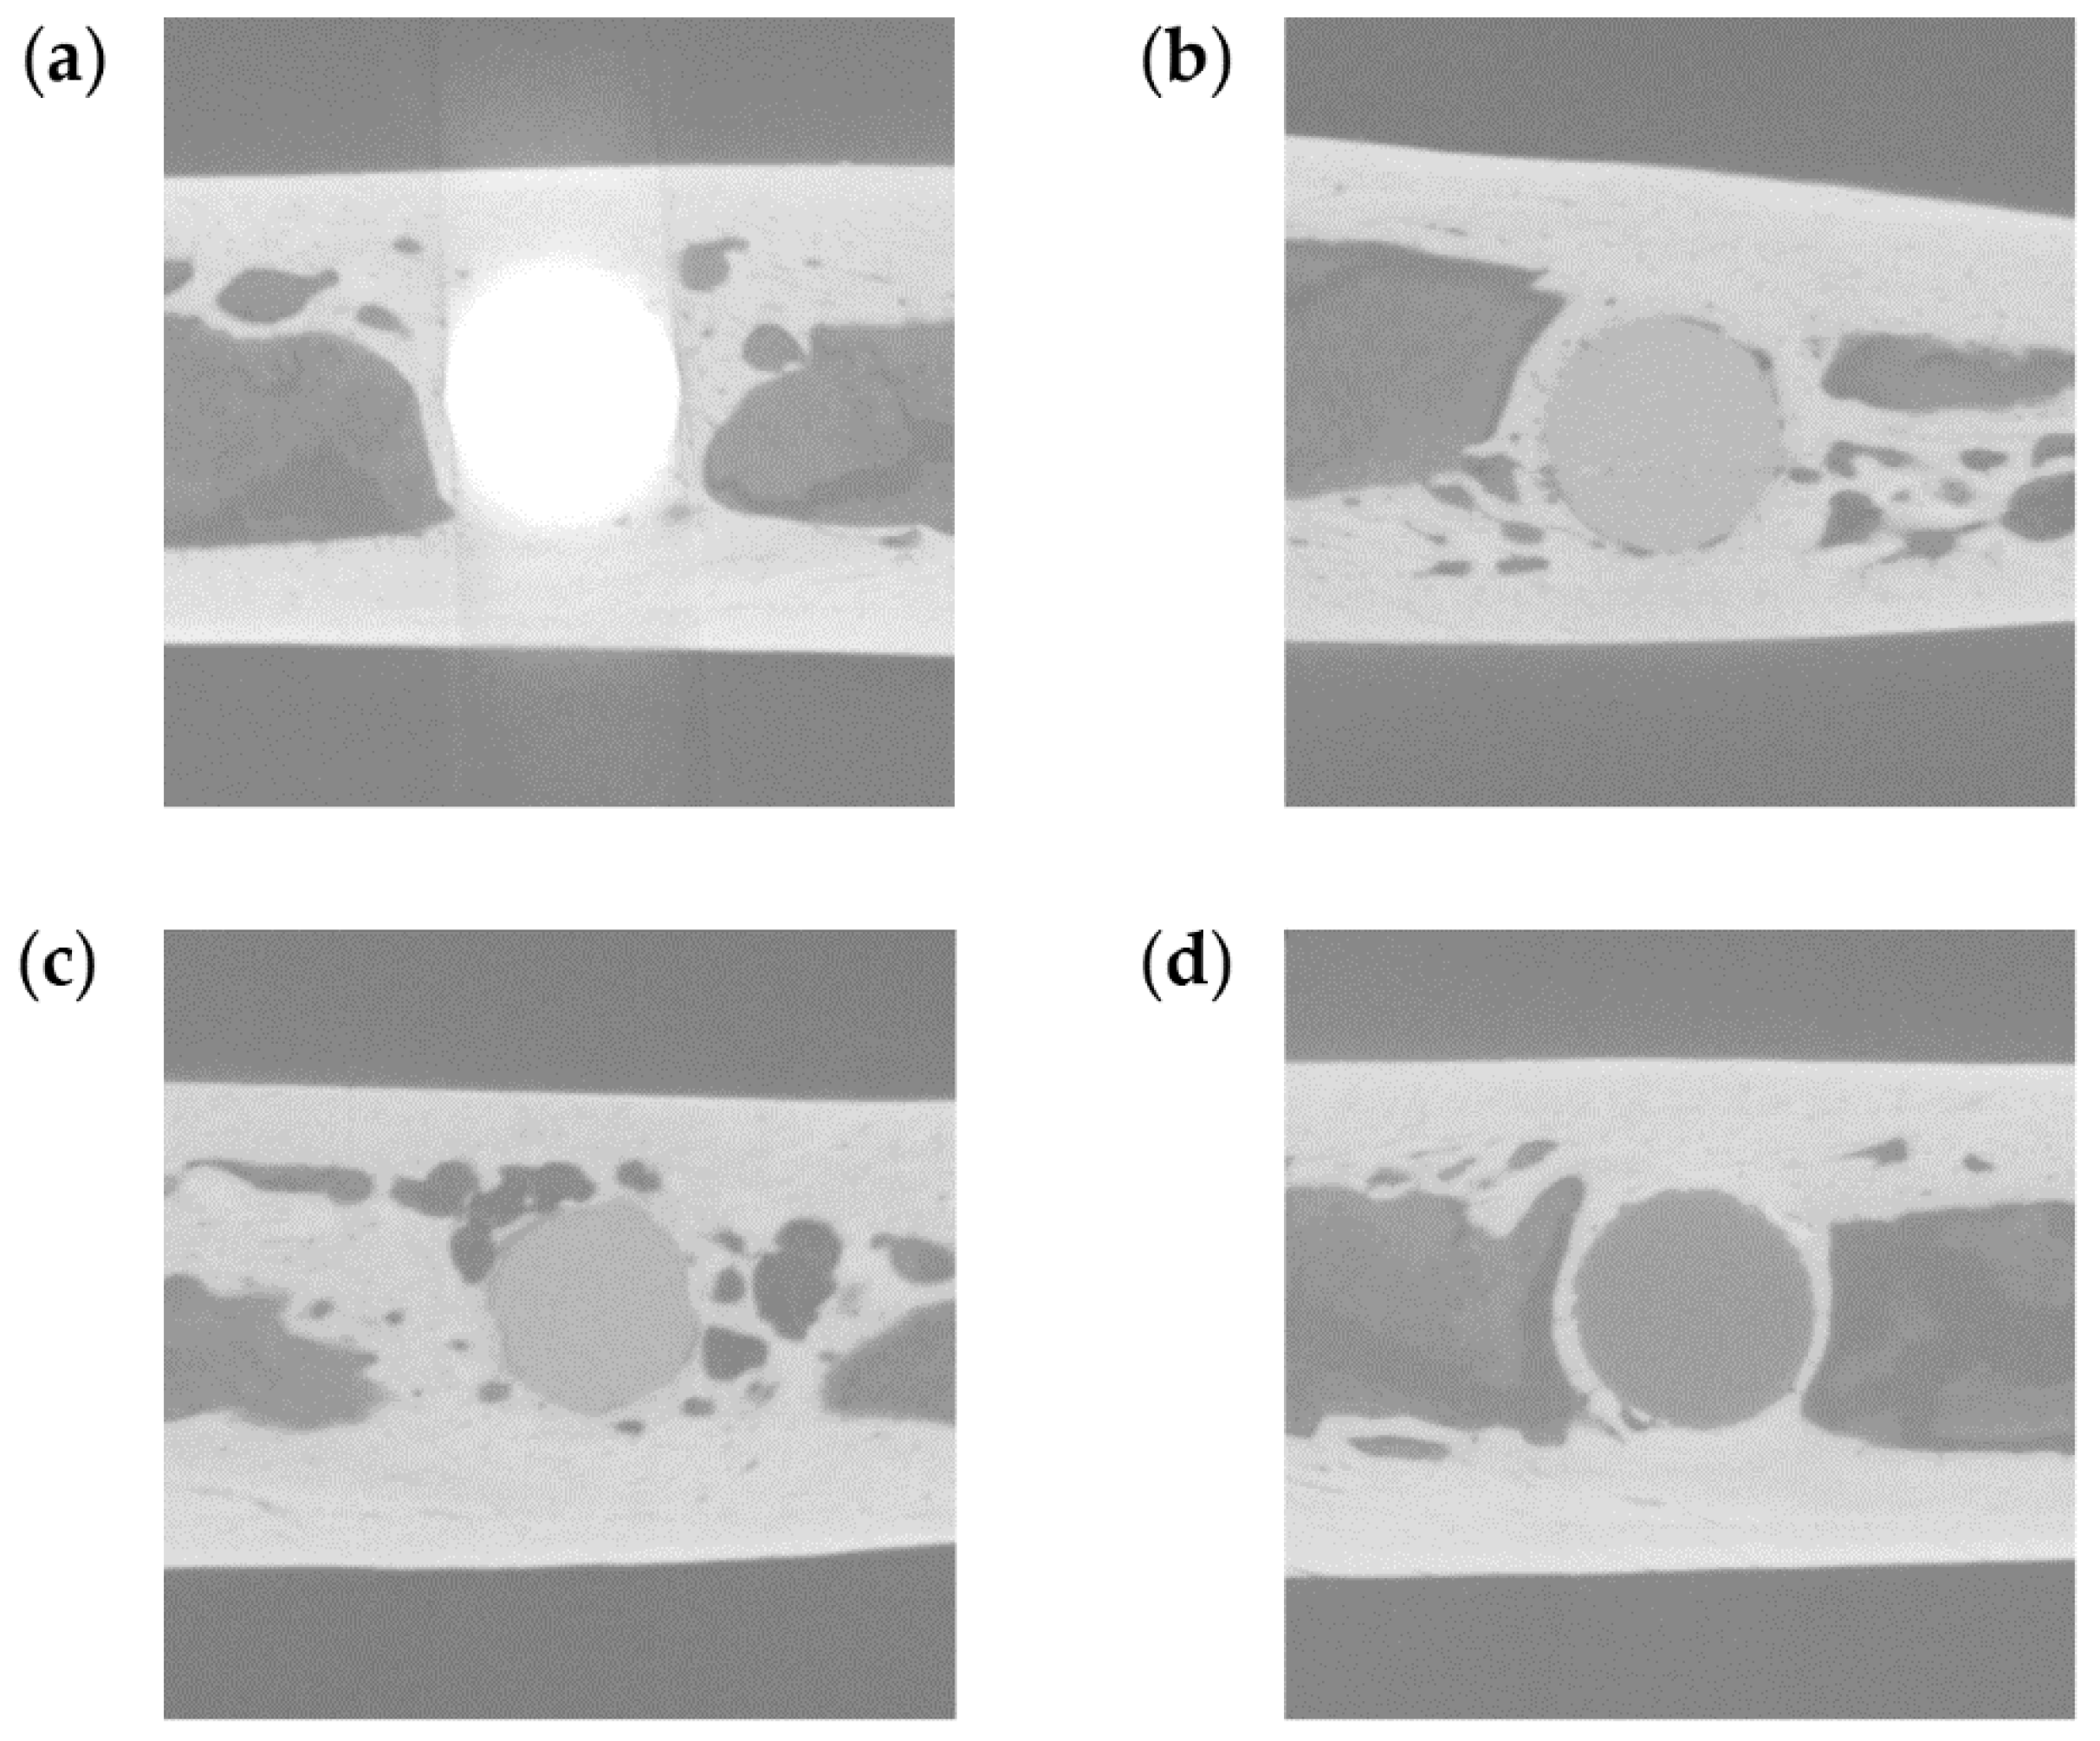

Figure 3.

Representative micro-computed tomography (CT) images. (a) TiA, (b) MgA, (c) Mg, and (d) PLA implants.

2.5. Three-Dimensional High-Resolution Micro-CT

The bone implant samples were scanned at room temperature using an inspeXio SMX-225CT system (Shimadzu Corporation, Kyoto, Japan) at a voxel size of 7 μm. To scan the TiA, MgA, Mg and PLA samples (which have different X-ray absorption coefficients) and cortical and cancellous bones without excess and deficiency, the system was operated at 70 kV, with a current of 160 μA and an integration time of 125 ms (Figure 3). A brass plate of 0.1-mm thickness was attached in front of the X-ray source to reduce beam hardening noise, which hampers analysis. The evaluation was conducted with the pins parallel to the rotation axis of the microCT, resulting in approximately 900–950 slices per sample. For each sample, 14 TiA, 12 MgA, 12 Mg and 16 PLA samples were used for micro-CT analysis. Of these, 18 were in two weeks, 17 in four weeks and 19 in 12 weeks.